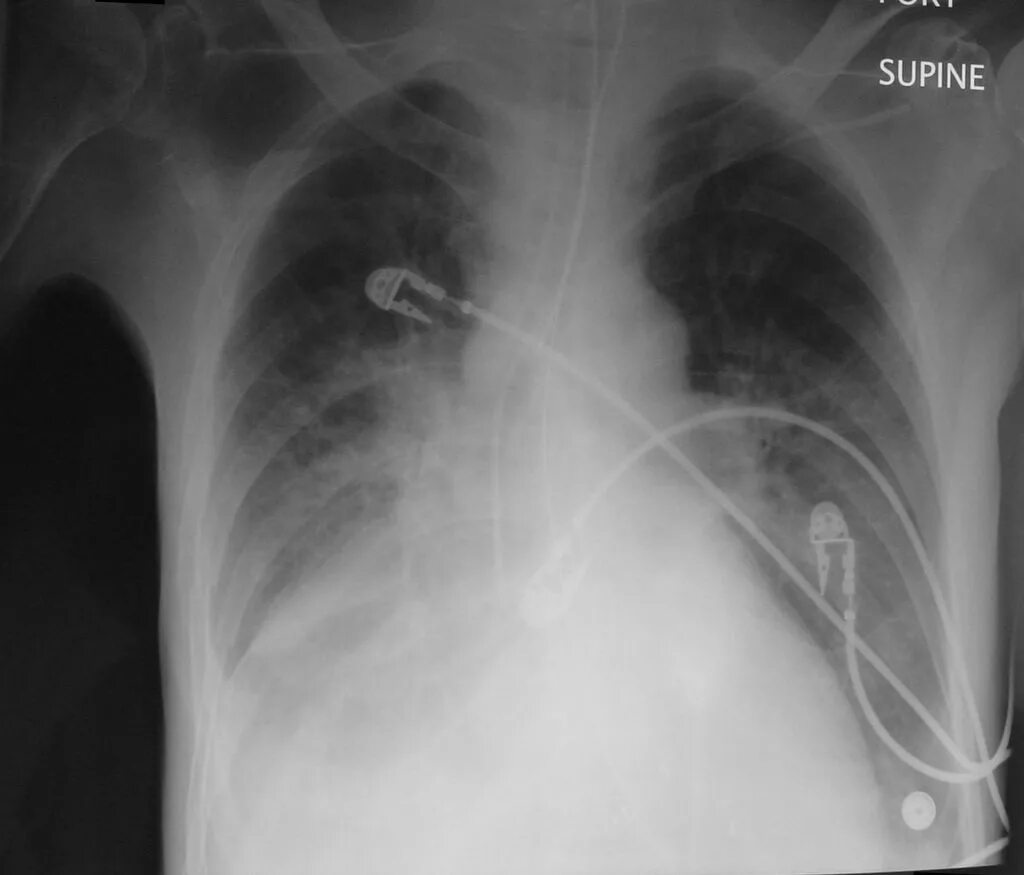

Диффузный эндобронхит